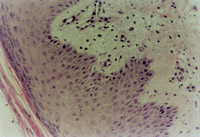

傷后12h急診入院,檢查雙下肢為淺Ⅲ度燒傷。創(chuàng)面表皮已壞死剝脫,真皮層變性壞死呈蠟黃色和蠟白色相間(圖5-3-1)。取局部組織做病理切片檢查,顯示上皮組織全層壞死,真皮層膠原纖維變性,結(jié)構(gòu)紊亂,微循環(huán)瘀滯(圖5-3-2)。

5-3-2 上皮組織全層壞死,膠原纖維變性,微循環(huán)瘀滯 HE×20